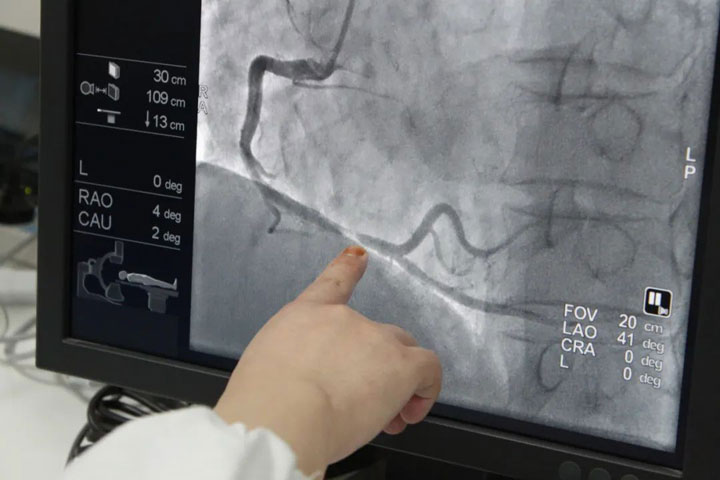

经过一系列详细检查结合病史,心内科桂陈主任诊断其为“不稳定型心绞痛、冠状动脉粥样硬化性心脏病”。随后,主任医师、集团心内科医疗中心李枫院长带领桂主任为其行冠脉造影,术中发现“右冠脉(RCA)近中段80%狭窄,中段80%狭窄,远段90%狭窄”,与家属沟通后,行介入治疗。术后,吴阿姨恢复良好,康复之际与家人共同送来锦旗,表达对医生护士的感谢。